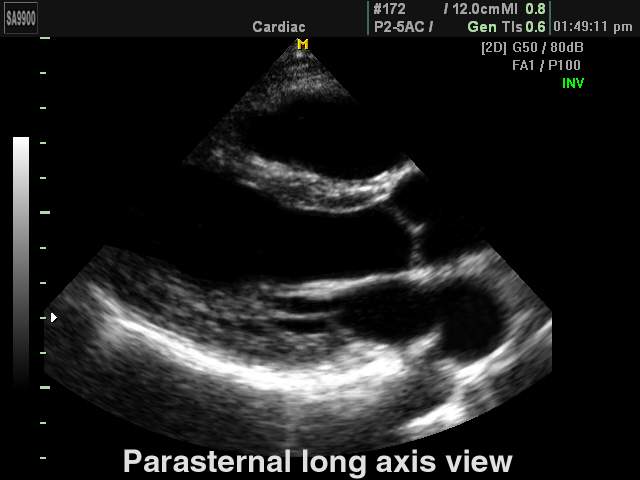

Heart (long axis of LV), B-mode

[RU] Ultrasound image №171: Heart (parasternal long axis of LV) in B-mode.

Echogramm was received by ultrasound scanner SonoAce-9900 (out of production).